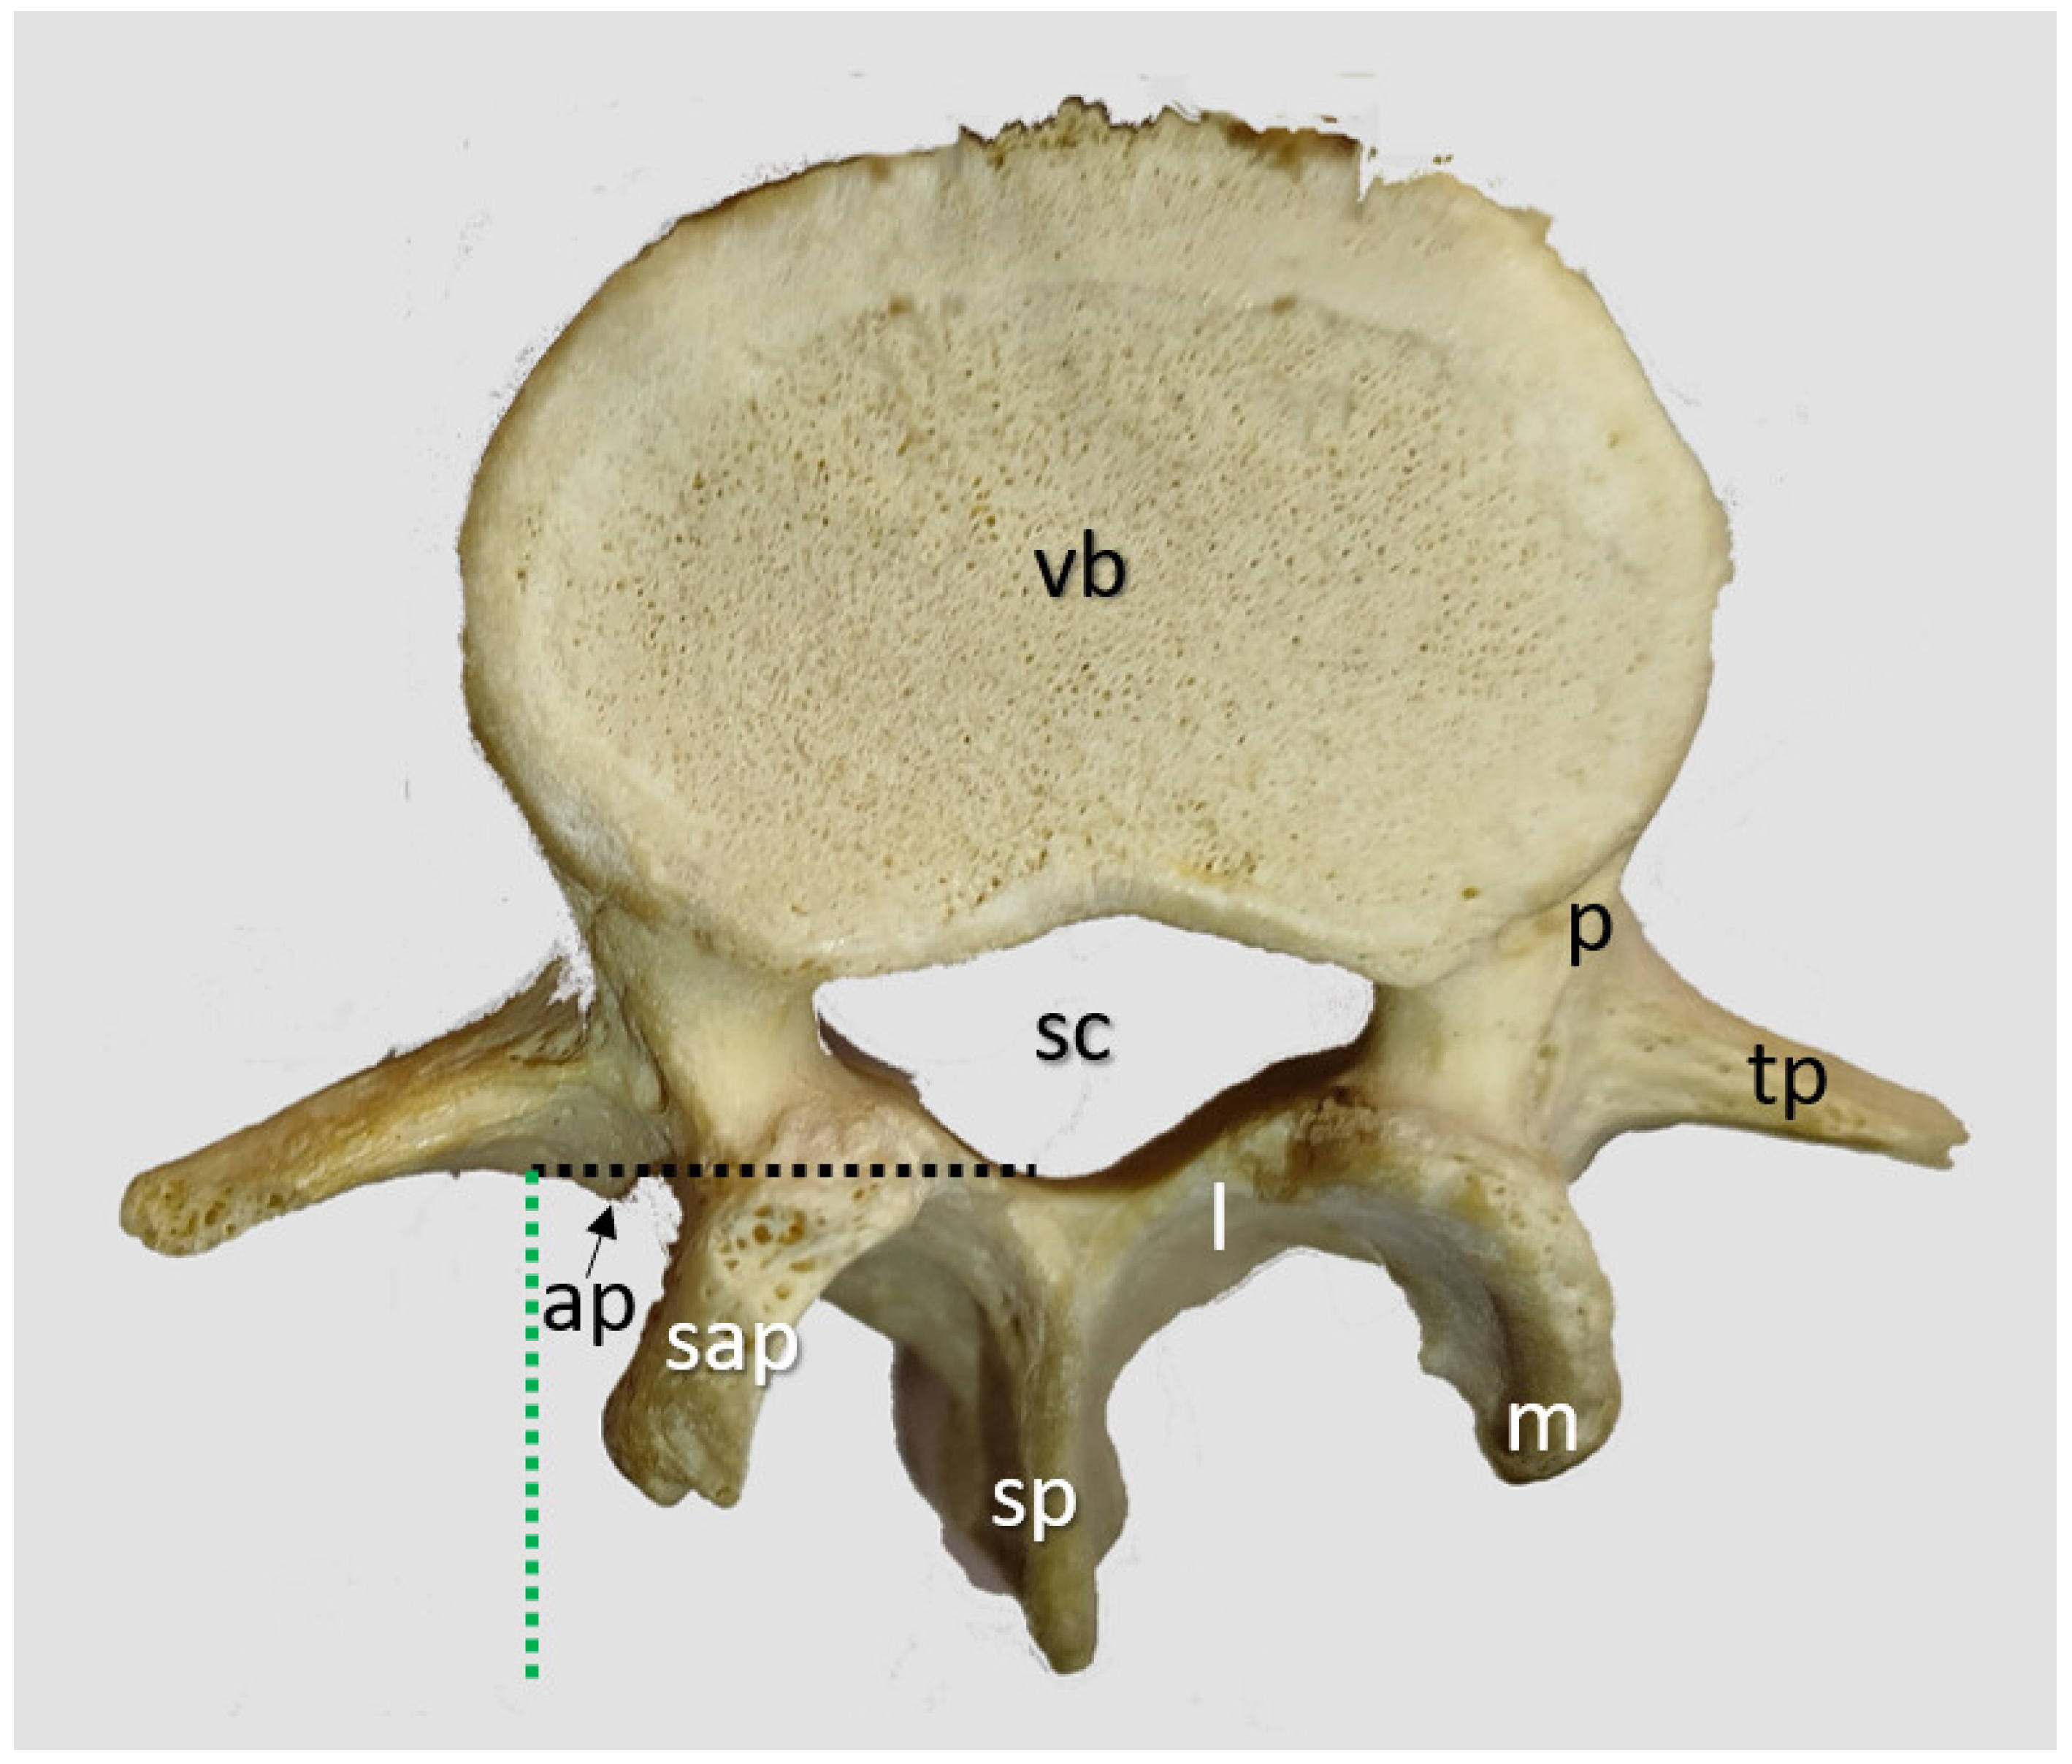

2.1.1. Transverse Process and Dural Sac Alignment

3.4.2. Lumbar Vertebrae